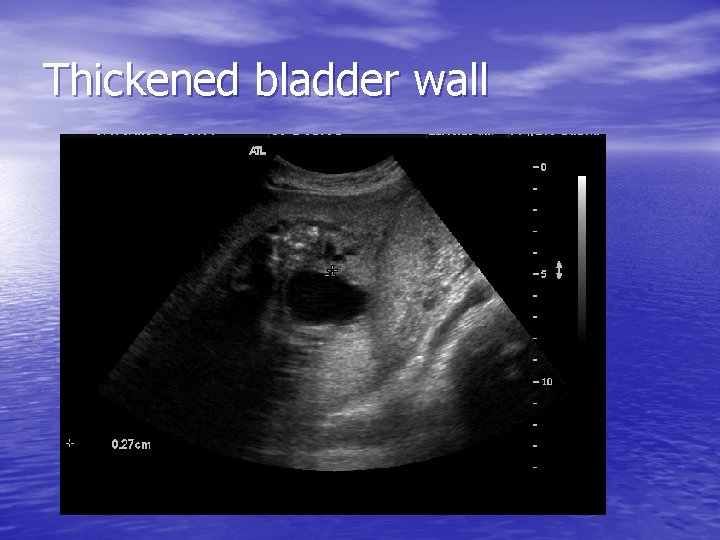

Thickened bladder wall

Work up – First step – ultrasound • Bladder evaluated prior to and following • • drainage by fine needle vesicocentesis Overall size of bladder and degree of proximal urethral dilation (keyhole sign) Urethral and kidney evaluation for dilation or abnormalities, echogenicity, or cysts After vesicocentesis – the degree of bladder thickness is assessed Rule out other anomalies ie NTD, cardiac defects

PUVS - Findings • Histologically – Smooth muscle hypertrophy and • • hyperplasia within the bladder wall – increased bundle of smooth muscle Dilation of distal and proximal tubules associated with peritubular and interstitial fibrosis Fibrosis = echogenic appearance of the renal parenchyma on ultrasound